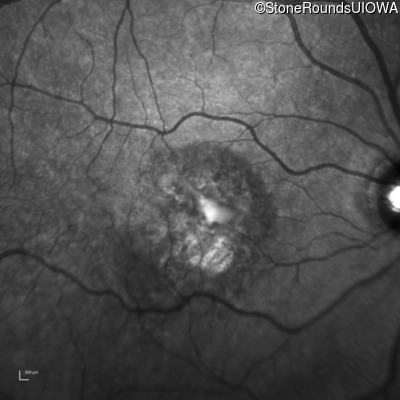

Infrared Fundus Photograph - Left - 20/125 -2

Exemplar